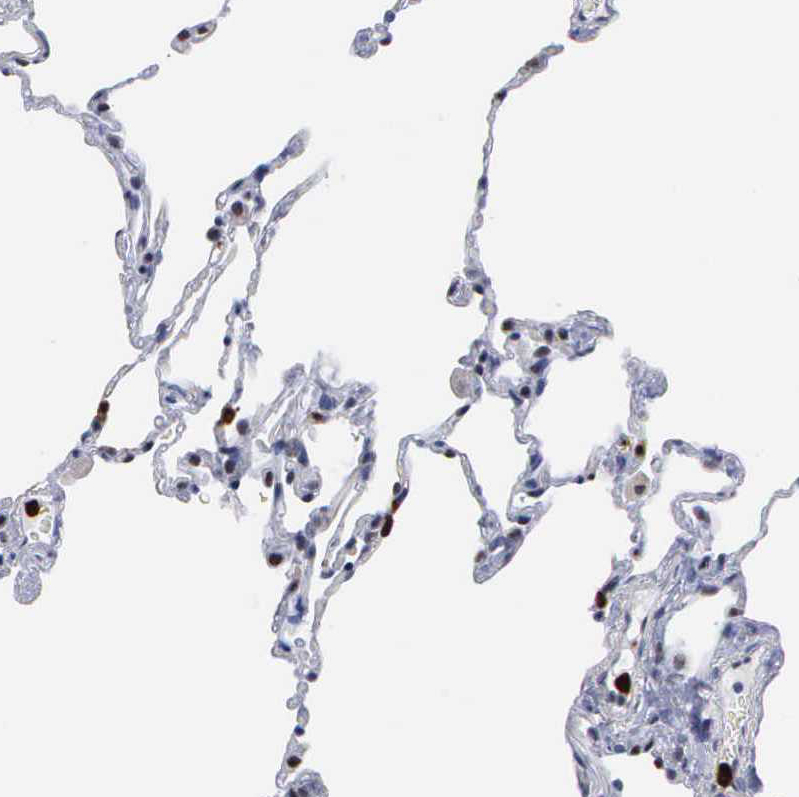

Immunohistochemical staining of human lung shows strong nuclear positivity in macrophages.